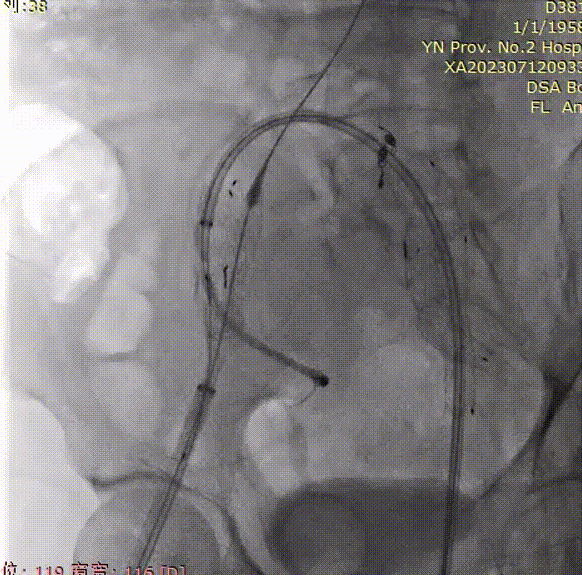

支架植入前造影

双侧股动脉入路,左侧置入18Fr 33cm GORE® DrySeal 亲水涂层导引鞘(以下简称“DSF导引鞘”),右侧置入12Fr 45cm DSF导引鞘;建立翻山通路后将标记猪尾导管头端置于肾动脉开口上方,做腹主动脉造影:显影显示双侧髂总动脉瘤;肾动脉开口到右髂内距离约200mm。